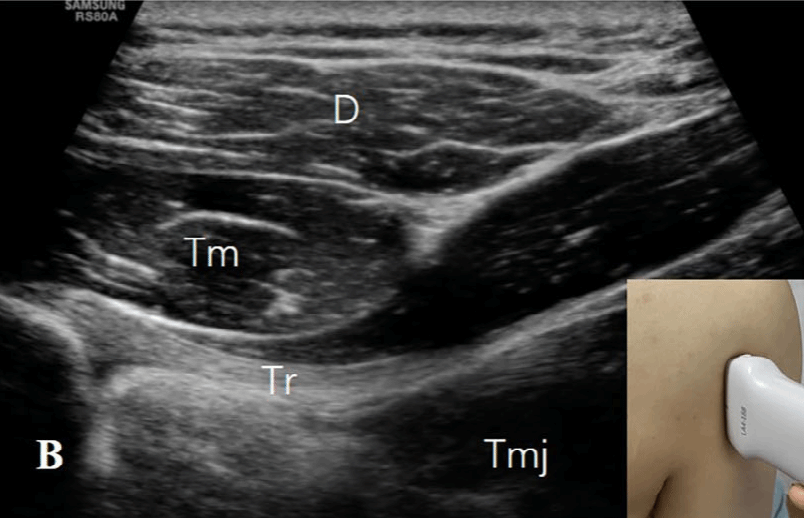

探头的位置根据三个解剖标志来确定:四边孔、肩胛下肌的前方和腋动脉的后方。1)四边孔:由上方的小圆肌、下方的大圆肌、内侧的肱三头肌长头和肱外侧的骨外科颈构成。在评估这个区域时,患者取坐位,肩部处于中立位置。探头沿纵向放置在肩胛骨的外缘和肩胛骨下角下方,以显示冈下肌和小圆肌的短轴切面(图2A)。探头沿着矢状面向外侧移动,直到出现肱三头肌长头腱(图2B)。在这一切面上,小圆肌位于肱三头肌长头的头侧和浅方,大圆肌位于足侧和深方。探头继续向外侧移动,直到出现肱骨干(图2C)。在此切面上,腋神经(AN)和旋肱后动脉位于由头侧的小圆肌(Tm)、足侧的肱三头肌长头(Tr)、浅方的三角肌(D)和深方的肱骨干围成的空间内。通过调整探头,可以更清楚地显示神经血管束(图2D)。

图2B:探头向外侧移动,直到出现肱三头肌长头腱(Tr)(图1B)。在这个水平上,小圆肌(Tm)位于肱三头肌长头的头侧和浅方,大圆肌(Tmj)位于足侧和深方。